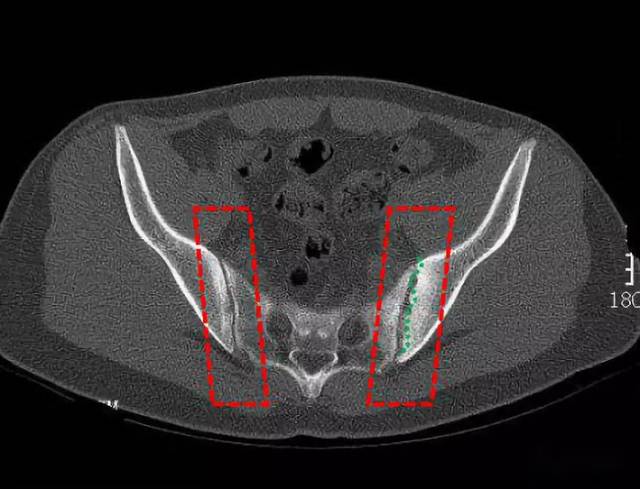

ct49324:强直性脊柱炎

图片尺寸1024x778